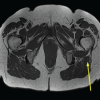

At his first visit, the patient was given a Medrol Dospak (methylprednisolone 4 mg) to address suspected cervical radiculopathy. Eight days later, an MRI was performed of the cervical spine which revealed (1) degenerative changes of the cervical spine most prominent at C5–6 with moderate spinal canal stenosis, cord deformity and cord edema signal, moderate left, mild right foraminal stenosis, and (2) at C6–C7, right paracentral and right foraminal disk herniation causing mild spinal canal stenosis, cord deformity, and severe right foraminal stenosis (Fig. 1 and 2). Subsequent follow-up with a fellowship-trained orthopedic spine surgeon revealed improving symptoms, but now with 4+/5 right wrist extension strength and positive Hoffmann’s bilaterally. At this time, it was recommended that the patient not return to play due to concern regarding the cord edema. Over the course of the next month and a half, his numbness and tingling worsened with prolonged sitting, and he was starting to notice difficulty with push-ups due to weakness in his right pectoralis major muscle. He presented for a follow-up visit now ~3 months post injury. On physical examination, he demonstrated 4/5 right biceps and right triceps strength. In addition, finger extensors were 4/5 bilaterally. Sensory examination showed no focal deficits in the upper extremities. At this visit, surgical intervention was recommended and described as C5–6 and C6–7 anterior discectomy with arthroplasty with possible fusion with allograft plating. A C5–6 and C6–7 anterior discectomy and arthroplasty were performed exactly 3 months after the initial office visit by a fellowship-trained spine surgeon (Fig. 3). Three weeks postoperatively, the patient presented with resolution of arm pain, numbness, or tingling, taking ibuprofen as needed for pain related to surgery site. Upper extremity motor examination was intact bilaterally C5–T1 except mild wrist flexor weakness bilaterally (5−/5). Sensory examination revealed intact sensation bilaterally. Cervical range of motion in all planes (bilateral rotation, lateral bending, flexion, and extension) was normal and painless. Post-operative X-rays demonstrated the C5–7 disk arthroplasties in good position.